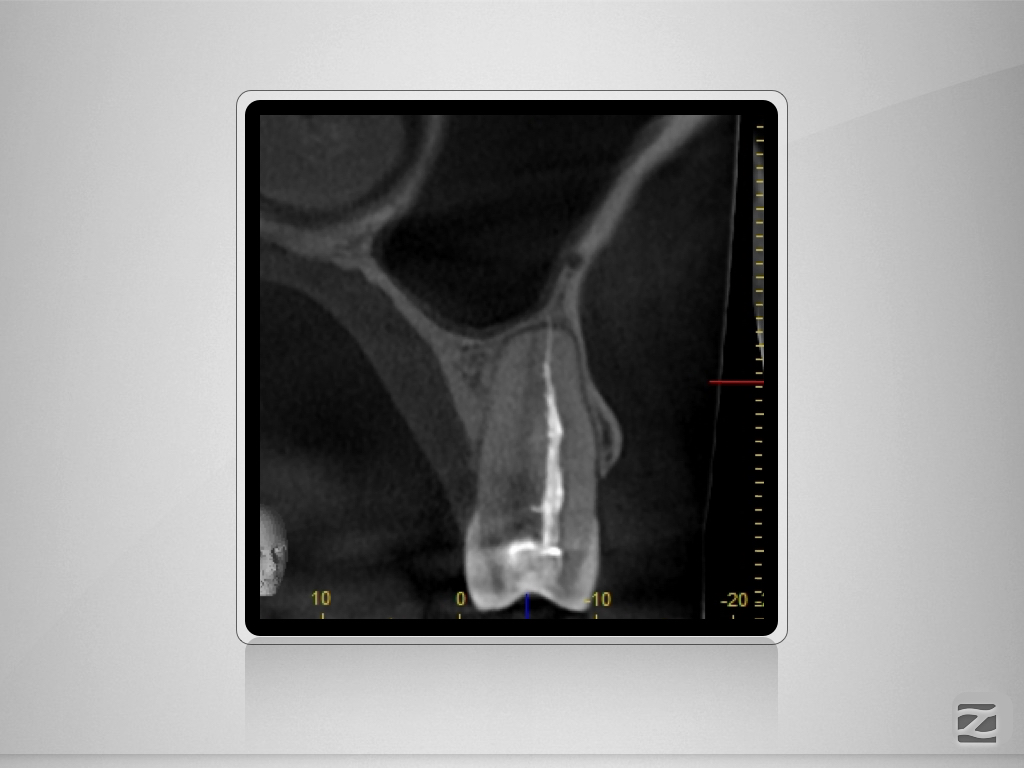

25D.003

1024 × 768

Vertucci Typ VII